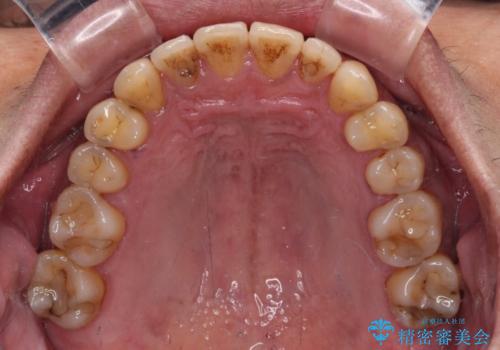

前歯のクロスバイトを改善 ワイヤー装置での非抜歯矯正

- クリアブラケット

上下の叢生は速やかに改善できましたが、右側のクロスバイトの改善に1年以上の期間を要しました。